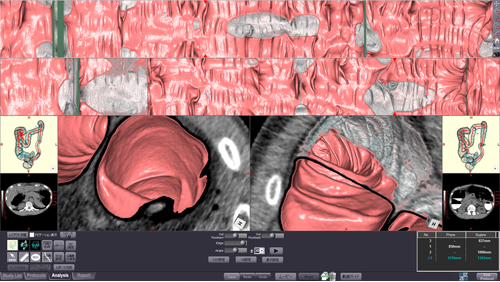

造影剤により標識されたタギングデータに対応し,残渣や残液を電子的に除去するデジタルクレンジング処理が可能になりました。クレンジングモードのOn/Offの切り替えも可能です。

また,腸管の自動抽出を自動前処理として設定することが可能になったほか,操作性も一層向上しました。

図6 CT大腸解析